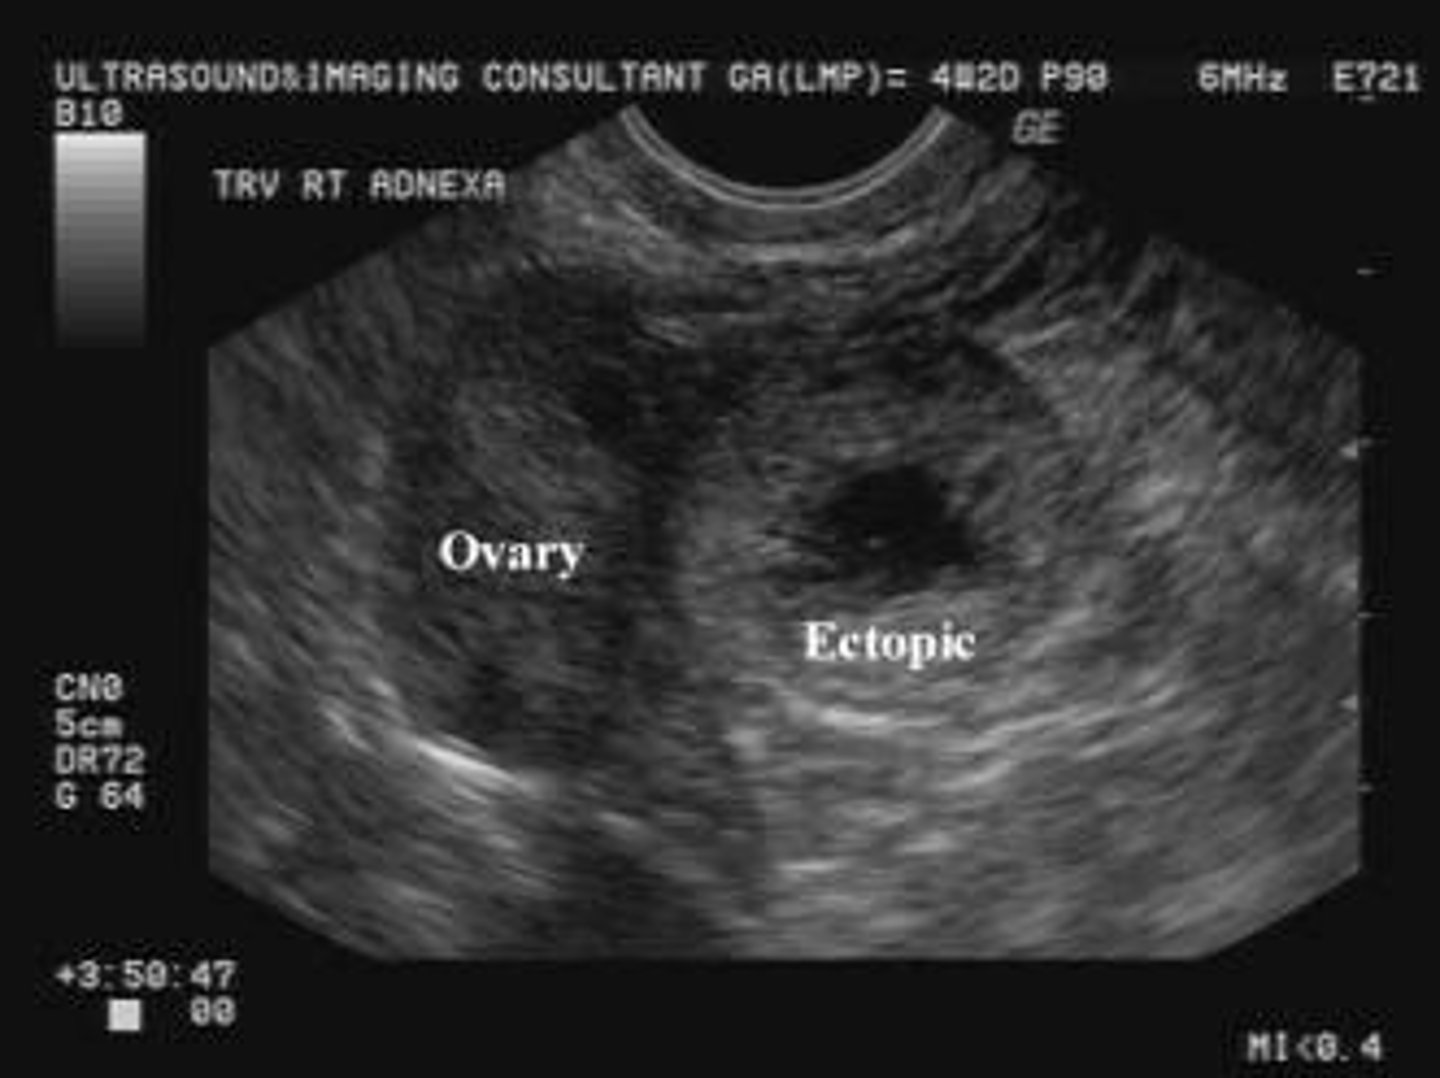

What is the classic clinical triad for an ectopic pregnancy?

Amenorrhea, vaginal bleeding, and pelvic pain.

What are the diagnostic criteria for an ectopic pregnancy using TVUS?

An empty uterus combined with a tubal ring sign (gestational sac outside the uterus).